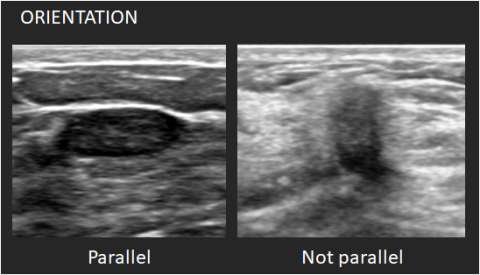

Orientation: Orientation is defined with reference to the skin line. Parallel or “wider-than-tall” orientation is often a characteristic of benign masses; however, it should not be the sole feature when assessing for likelihood of malignancy.

1. Parallel: The long axis of the mass parallels the skin line.

2. Not parallel: The long axis of the mass is not parallel to the skin line.

Ultrasounds Mass Orientation